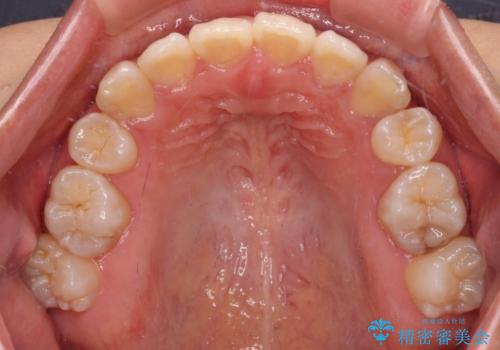

非接触の前歯と下顎のデコボコ ワイヤー装置による矯正治療

- 上下顎前歯部の非接触(開咬)と下顎のデコボコを主訴に来院された患者様です。

右側上下と左上の小臼歯が一本ずつ少なく、さらに骨格的な左右差もあり上下の真ん中の位置がずれています。

下顎のデコボコの解消と、真ん中の位置を改善するために左下の小臼歯を抜歯することとしました。

また、開咬を改善するため臼歯部にアンカースクリューを用いて圧下する力をかけていきました。

舌を突出する癖があり、それにより開咬が悪化したり、後戻りの原因になるため、舌のトレーニング(MFT)も行いました。